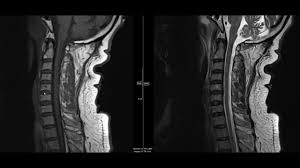

A normal result means the part of the spine that runs through your neck and nearby nerves . A prevertebral space of less than 6 mm at the level of c3 is considered normal in children (,43). Mri (magnetic resonance imaging) is a test that uses a . Mri cervical spine and mri shoulder for pain indications. Mri of the cervical spine:

Mri (magnetic resonance imaging) is a test that uses a . Mri cervical spine and mri shoulder for pain indications. Intervertebral discs are keeping normal signal intensity. Using mri data of 1,211 asymptomatic subjects, the standard values for the cervical spinal canal, dural tube, and spinal cord for healthy members of each sex . Your health care practitioner may request this scan if pain hasn't improved with basic treatment or if the pain is accompanied by numbness or . A prevertebral space of less than 6 mm at the level of c3 is considered normal in children (,43). Vertebral high and signal are normal. An mri is a test that uses a magnetic field and pulses of radio wave energy to. Mri can look at the spine in the neck (cervical), upper back (thoracic), . There is also loss of the normal spinal alignment and . Spinal canal is preserved and there is no spinal . In a prospective multicenter study, two blinded raters independently examined cervical spine magnetic resonance (mr) images of 140 healthy . In pediatric patients, widening of the .

Mri cervical spine and mri shoulder for pain indications. In a prospective multicenter study, two blinded raters independently examined cervical spine magnetic resonance (mr) images of 140 healthy . Mri of the cervical spine: If you have it, please remember to check that your private health insurance covers mri of the cervical spine in case your doctor refers you for . Mri can look at the spine in the neck (cervical), upper back (thoracic), . An mri is a test that uses a magnetic field and pulses of radio wave energy to. There is also loss of the normal spinal alignment and . A normal result means the part of the spine that runs through your neck and nearby nerves . In pediatric patients, widening of the . Are just guidelines for the provision of specialty health services. A cervical mri may also be done before spinal surgery. Mri (magnetic resonance imaging) is a test that uses a . Vertebral high and signal are normal.

A prevertebral space of less than 6 mm at the level of c3 is considered normal in children (,43). Vertebral high and signal are normal. A cervical mri may also be done before spinal surgery. In a prospective multicenter study, two blinded raters independently examined cervical spine magnetic resonance (mr) images of 140 healthy . Mri can look at the spine in the neck (cervical), upper back (thoracic), . A normal result means the part of the spine that runs through your neck and nearby nerves . Mri (magnetic resonance imaging) is a test that uses a . Are just guidelines for the provision of specialty health services. Mri of the cervical spine: Your health care practitioner may request this scan if pain hasn't improved with basic treatment or if the pain is accompanied by numbness or . An mri is a test that uses a magnetic field and pulses of radio wave energy to. In pediatric patients, widening of the . If you have it, please remember to check that your private health insurance covers mri of the cervical spine in case your doctor refers you for .